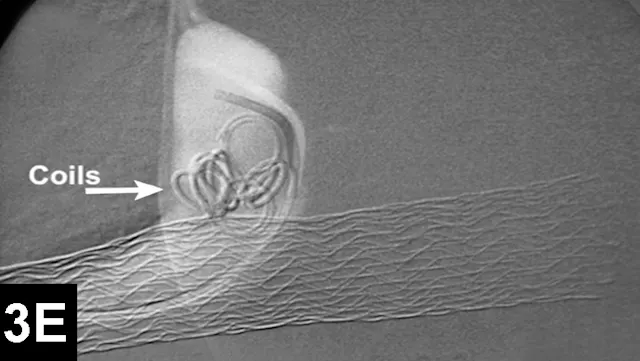

Figure 3A: Serial fluoroscopic images in a dog with a left divisional intrahepatic shunt.

The dog is in dorsal recumbency with the head to the left.

Double venogram of caudal vena cava (CVC) and portosystemic shunt (PSS) demonstrating entrance of shunt (*) into CVC.